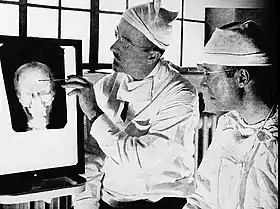

"Dr. Walter Freeman, left, and Dr. James W. Watts right, study an X-ray before a psychosurgical operation. Psychosurgery is cutting into the brain to form new patterns and rid a patient of delusions, obsessions, nervous tensions and the like." Waldemar Kaempffert, "Turning the Mind Inside Out", Saturday Evening Post, 24 May 1941.[1] | |

The first prefrontal leucotomy in the United States was performed at the George Washington University Hospital on 14 September 1936 by the neurologist Walter Freeman and his friend and colleague, the neurosurgeon, James W. Watts.[125] Freeman had first encountered Moniz at the London-hosted Second International Congress of Neurology in 1935 where he had presented a poster exhibit of the Portuguese neurologist's work on cerebral angiography.[126] Fortuitously occupying a booth next to Moniz, Freeman, delighted by their chance meeting, formed a highly favourable impression of Moniz, later remarking upon his "sheer genius".[126] According to Freeman, if they had not met in person it is highly unlikely that he would have ventured into the domain of frontal lobe psychosurgery.[127] Freeman's interest in psychiatry was the natural outgrowth of his appointment in 1924 as the medical director of the Research Laboratories of the Government Hospital for the Insane in Washington, known colloquially as St Elizabeth's.[128] Ambitious and a prodigious researcher, Freeman, who favoured an organic model of mental illness causation, spent the next several years exhaustively, yet ultimately fruitlessly, investigating a neuropathological basis for insanity.[129] Chancing upon a preliminary communication by Moniz on leucotomy in the spring of 1936, Freeman initiated a correspondence in May of that year. Writing that he had been considering psychiatric brain surgery previously, he informed Moniz that, "having your authority I expect to go ahead".[130] Moniz, in return, promised to send him a copy of his forthcoming monograph on leucotomy and urged him to purchase a leucotome from a French supplier.[131]